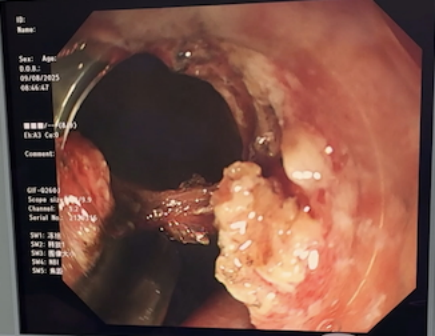

(圖為內(nèi)鏡醫(yī)師在內(nèi)窺鏡下對(duì)十二指腸腫瘤進(jìn)行全層切除)

8月9日,手術(shù)正式進(jìn)行。在此次采用的通過(guò)腹腔鏡聯(lián)合內(nèi)鏡的雙鏡模式中,外科醫(yī)師首先通過(guò)腹腔鏡提前游離暴露十二指腸,然后內(nèi)鏡醫(yī)師通過(guò)內(nèi)鏡準(zhǔn)確找到腫瘤并精準(zhǔn)切除。由于提前對(duì)十二指腸的充分游離,并使用紗布隔離了下腔靜脈、膽囊、膽管,內(nèi)鏡醫(yī)師不必?fù)?dān)心切穿十二指腸,可以專(zhuān)注于腫瘤的精準(zhǔn)切除,大大減少了操作難度。一旦切穿十二指腸或十二指腸局部薄弱的情況下,外科醫(yī)師再立即進(jìn)行十二指腸修補(bǔ),之后再由內(nèi)鏡醫(yī)師對(duì)修補(bǔ)處進(jìn)行檢查,并放置胃管或者三腔營(yíng)養(yǎng)管。